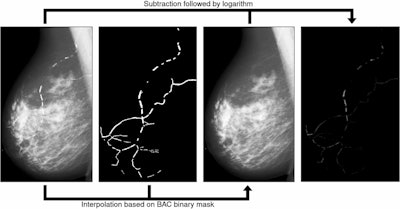

Molloi and co-authors developed their DL model with the goal of detecting, segmenting, and quantifying BAC in mammograms. Their goal included improving mammographic screening for cardiovascular risk assessment. The model employed a modified U-Net architecture that incorporates Hausdorff loss (for better finding BAC boundaries), Dice loss, and binary cross-entropy loss for segmentation and later quantification.